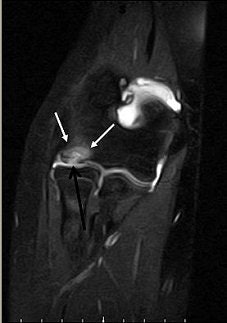

![]() |

| Same patient as above. Top, sagittal T1-weighted MR image of elbow shows lesion (arrow) as large area of signal abnormality with low-signal-intensity rim and heterogeneous intermediate signal intensity and low signal intensity centrally. Below, sagittal fat-suppressed T2-weighted fast spin-echo MR image of elbow shows osteochondritis dissecans lesion (arrow) as large area of signal abnormality with high-signal-intensity rim and linear bands of high and low signal intensity centrally. Note marked irregularity of articular cartilage overlying osteochondritis dissecans lesion (arrowhead). |

| Kijowski R and De Smet AA, "MRI Findings of Osteochondritis Dissecans of the Capitellum with Surgical Correlation" (AJR 2005; 185:1453-1459). |